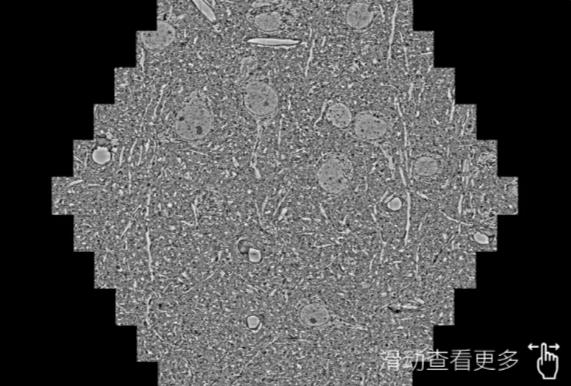

鼠脑切片。左图使用昌江蔡司昌江扫描电镜MultiSEM706对165μmx143pm面积区域成像,耗时仅需1.5秒。右图为鼠脑切片中30μm区域放大效果。样品由芝加哥大学B.Kasthuri提供。

使用蔡司高速昌江扫描电镜MultiSEM对1mm²人脑皮层组织进行高分辨成像,并对其中的各种细胞结构进行三维重构分析。左图展示了2x3mm²组织平面中锥体神经元的三维重构效果。右图显示了局部体积神经元三维重构。图像由哈佛大学chtman实验室提供,渲染图由D. Berger 制作。